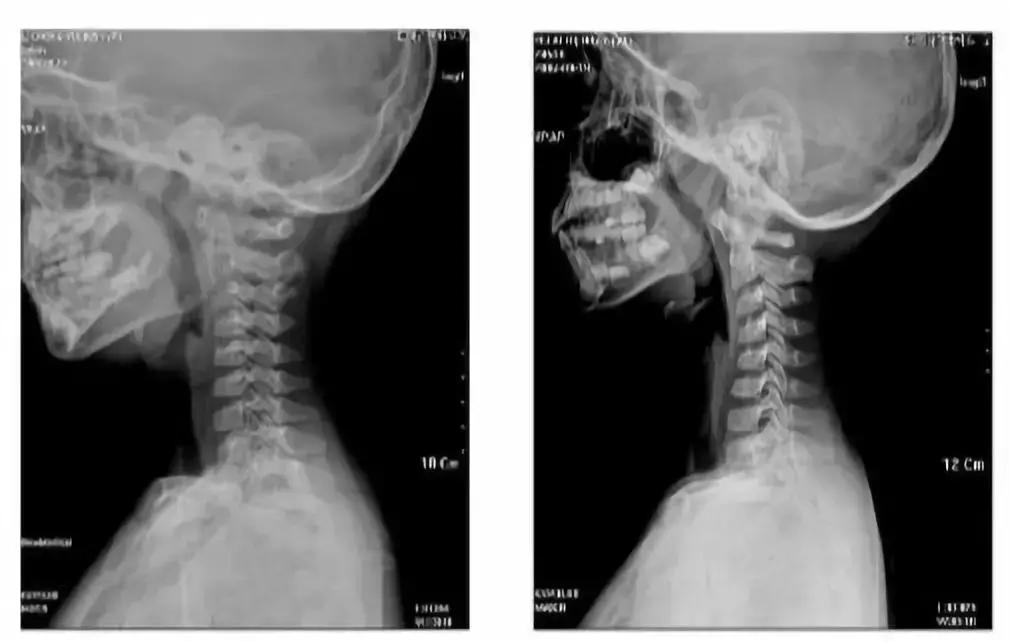

低头、坐姿不良的时间越长,对孩子的颈椎伤害越大,会出现颈椎自然曲度消失、变直或者反弓的情况,严重时还会出现寰枢关节半脱位。

颈椎反弓,指的是每个人的颈椎是有自然生理曲度的,长期低头会使颈椎的生理曲度发生变化,甚至向着反方向弯曲,形成“反弓”。

左:5岁孩子的颈椎生理曲度变直 右:7岁孩子的颈椎生理曲度呈“反弓”